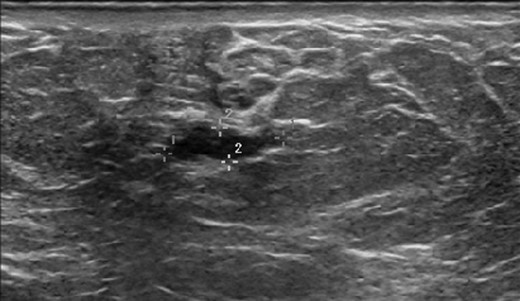

Bilateral mammogram demonstrated mild gynecomastia in both sides with no discrete mass or clusters of microcalcifications (Fig. 1). A follow-up ultrasound around the area of palpable concern did show a prominent duct with irregular contours at the 6:00 position in the left breast (Fig. 2). Excisional biopsy was recommended and a subareolar biopsy of the left breast was performed.

Ultrasound of the left breast at the 6:00 region reveals a mildly hypoechoic mass with ductal extension.